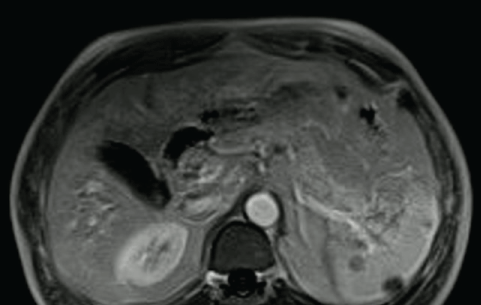

A 53-year-old man, with history of paranoid schizophrenia, depression, alcohol abuse, type 2 diabetes mellitus, comes to our observation for the discovery of focal splenic lesions. He presented fatigue and weight loss. Her past clinical history was negative for infection, abdominal pain, fever or sweat. Physical examination was characterized by cachexia in the absence of lymphadenomegaly and hepatosplenomegaly. Laboratory tests were negative, except for the C. burnetii antibodies (phase I IgG 1/128, phase II IgG 1/400 and negative IgM). Biological liver and kidney function were normal. Hepatitis B, hepatitis C, HIV, EBV, CMV serology were negatives. Positron emission tomography (PET) showed more hypermetabolic splenic lesions, distal small intestine hypercaptation associated with mesenteric lymph nodes and a right sub-clavicular lymph node (Figure 1). The splenic lesions had been confirmed by abdominal magnetic resonance imaging (MRI) (Figure 2). Colonoscopy showed inflammatory polipoyd lesions of the distal small intestine and uncomplicated diverticular colic disease. Gastroscopy, pulmonary scan, transesophageal echocardiography and bone marrow biopsy showed negatives. Doxycycline 200 mg b.i.d. and rifampicine 600 mg daily for three months treatment was initiated. In the absence of any improvement, after adequate vaccination for meningococcus, pneumococcus and haemophilus, splenectomy was carried out. The histopathological examination highlighted diffuse granulomatous process with multinucleated cells, mononuclear infiltrates, necrosis and fibrinous exudation. Coxiella burnetii DNA was negative in PCR.

Figure 2: a,b) Confirmed splenic lesions by abdominal magnetic resonance imaging.